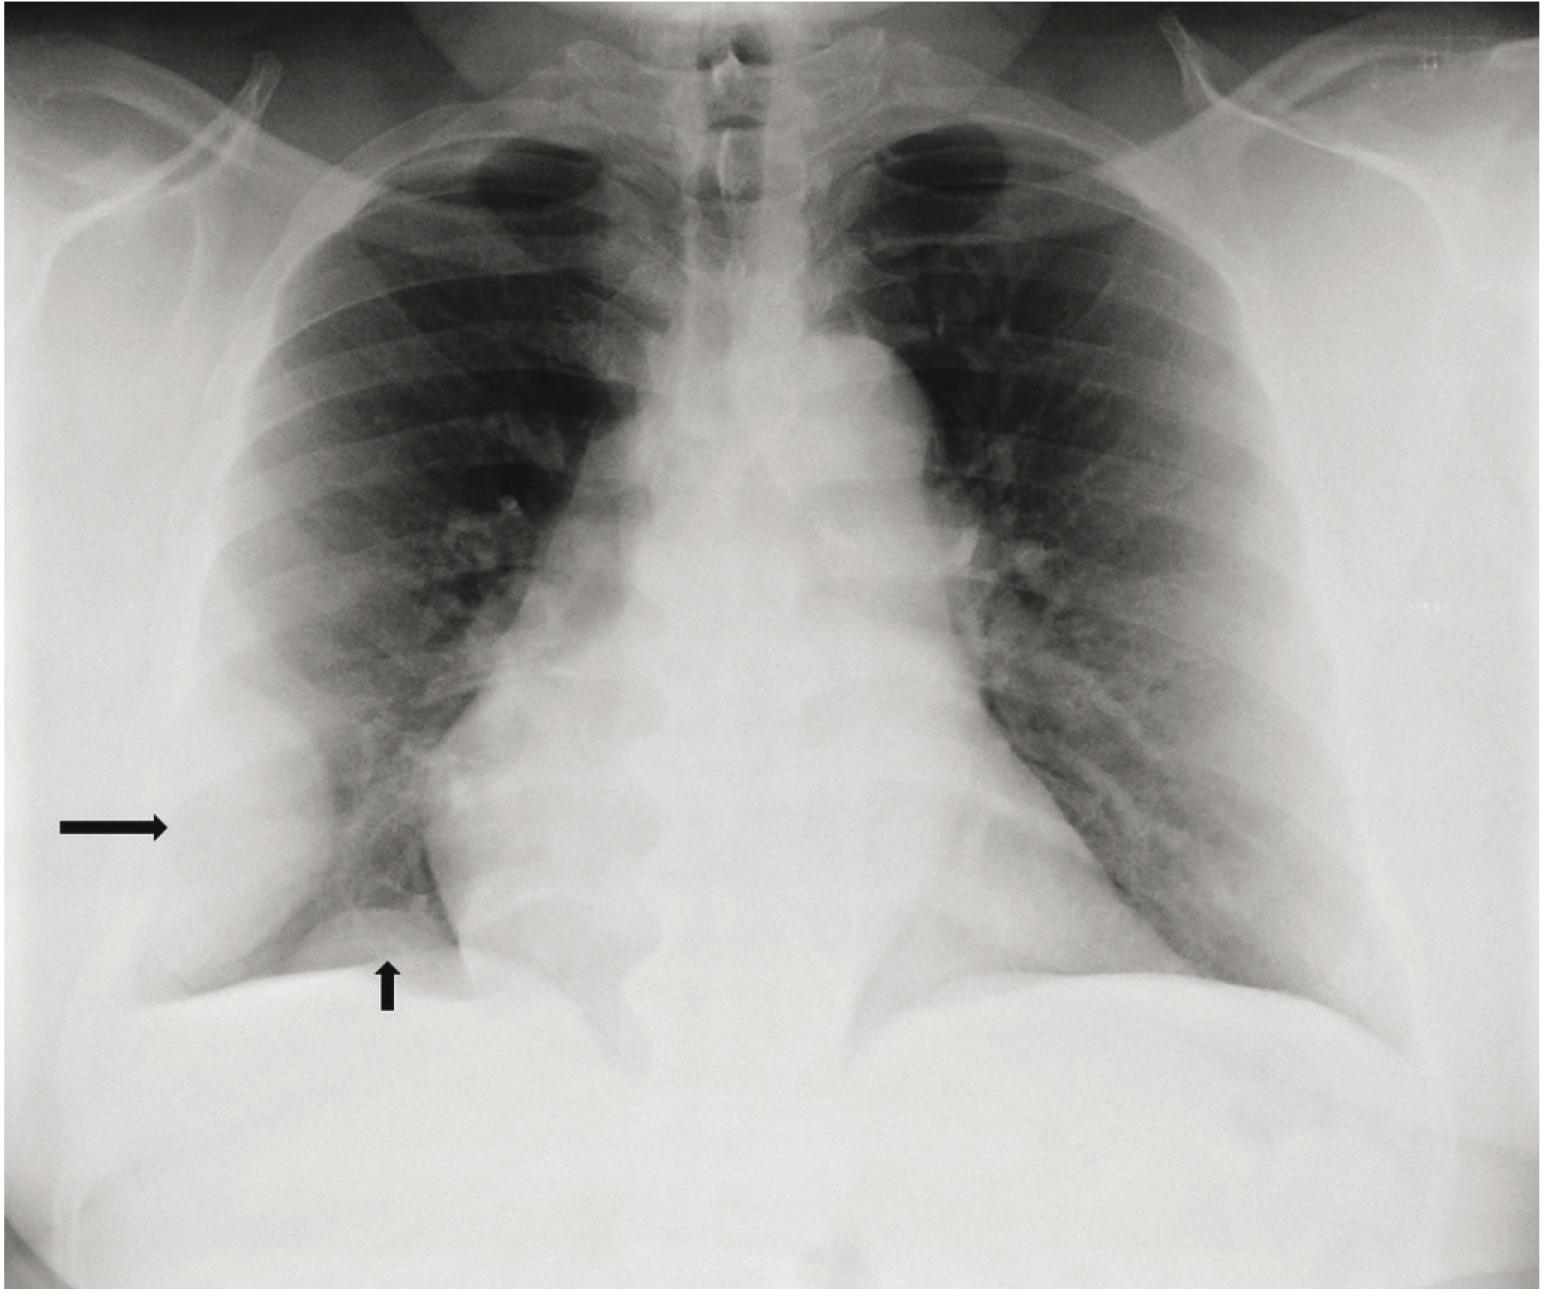

Vuhanu gde je izazvao brojne slučajeve upale pluća s nepoznatim . Uz to, dugorocni efekti su kumulativni – isto je 10 slika pluca u 10 dana ili u 10 . Kako bi shvatili šta virus može da uradi plućima, a onda i čitavom organizmu, bolnica Vašington D. Kasno otkrivanje karcinoma pluća je i osnovni razlog što je uspeh. Međutim, RTG pokazuje samo senku na plućima, što nije dokaz raka. Objawy raka płuca widoczne w badaniu RTG klatki piersiowej mogą być różnorodne – w zależności od lokalizacji raka, jego wielkości czy . Prilikom redovne kontrole kod interniste dobila sam uput za rendgen pluća i srca. Izveštaj sa rtg -a je sledeći: Hilobazalno obostrano izraženapl-šara po tipu . Karcinom pluća obuhvata više različitih tumora koji potiču iz raznovrsnih tkiva. RTG pregled pluća je jedan od pomoćnih dijagnostičkih pregleda, koji ima za cilj otkrivanje različitih strukturnih promena plućnog tkiva.